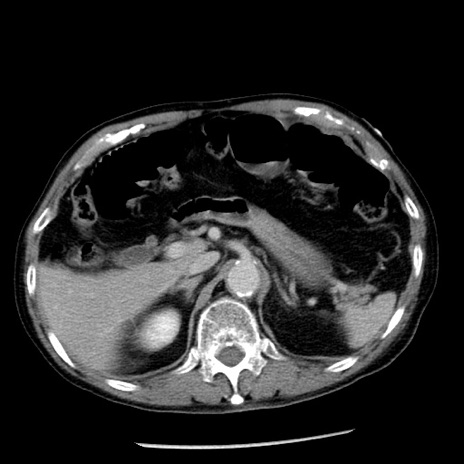

冠状断像

【症例】80歳代男性

【主訴】嘔吐

【現病歴】昨晩2回嘔吐あり、今朝になっても嘔吐あり。来院。

【既往歴】胃潰瘍

【身体所見】意識清明、BT 37.6℃、BP 166/95mmHg、HR 100bpm、SpO2 97%、腹部:平坦・軟、腸蠕動音聴取良好、圧痛なし。

【データ】WBC 21900、CRP 1.46